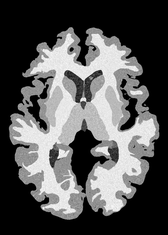

4.2 Registration to a 100 micron ex-vivo brain MRI volume

To showcase the efficacy of our method on real large scale images, we register a 250 in-vivo MRI image (Lüsebrink et al., 2017) to a 100 ex-vivo FLASH human brain volume (Edlow et al., 2019). This represents an inverse problem with more than 11.2B optimizable parameters (compared to 20M for clinical datasets), or 44.8GB of GPU memory. The entire problem does not fit on most GPUs, necessitating distributed multimodal registration. We optimize a composite transform - affine followed by a diffeomorphic mapping; details can be found in Section E.1. Multimodal deformable registration took 58 seconds on 8 NVIDIA A6000 GPUs, which is unprecedented at this resolution. Fig. 6 shows qualitative results, highlighting the ability to register highly detailed structures such as cerebellar white matter; these structures are not visible at macroscopic scales. The resultant advantages of performing registration at this scale can allow researchers to characterize the neuroanatomy at microscopic resolutions and allow morphometric analysis of cortical layers and subcortical nuclei among other structures.